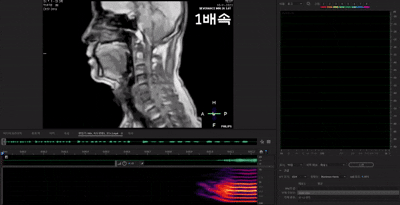

사단법인 세종대왕기념사업회는 지난 2023년부터 음성학과 성운학, 음성의학과 음성 공학 등의 융복합 연구를 통해 한국어 자음과 모음의 발음 과정을 정밀한 MR 영상으로 구현해 훈민정음해례본에 기록된 제자(製字·글자를 만드는 것) 원리와 발음을 검증하는 연구를 하고 있다.

다만 최 회장은 "CT의 경우는 동영상을 찍을 수 없다는 단점이 있다"며 "자기공명영상(MRI) 기법으로 분석한다면 더 좋지 않을까 생각했다"고 했다.

MRI로 '훈민정음' 제자 원리 밝힌다…한글 학습에 도움 될 수 있어

2023년도 연구비를 받게 되면서 꿈은 현실이 됐다. 첨단 영상 장비인 MRI 등을 이용해 자음과 모음을 발음할 때 일어나는 조음기관의 움직임과 성도의 모양 등을 입체적으로 규명할 수 있는 길이 열린 것이다. 최 회장은 "MRI는 연조직을 정확히 볼 수 있어 깨끗하게 관찰할 수 있다는 장점이 있다"고 설명했다.

세종대왕기념사업회의 연구 목적은 크게 세 가지로 나뉜다. 첫째는 훈민정음해례본에 기술된 상형의 실체를 MRI 기계를 통해 움직이는 영상으로 구현하는 것이다. 이를 바탕으로 훈민정음의 창제 의도와 원리 등을 과학적으로 입증하겠다는 계획이다.

게다가 연구를 통해 말소리, 특히 자음의 조음에 관한 정밀한 연구가 가능해질 수 있다. 특히 기존 연구에서는 혀의 움직임만을 부분적으로 또는 정밀하지 못하게 관찰했기 때문에 명확한 한계점이 있었다.

무엇보다도 '교육 측면'에서 이번 연구가 도움이 될 수 있다는 게 사업회의 설명이다. 자음과 모음의 조음 동작을 MR 영상으로 구현함으로써 교육용 콘텐츠를 제작해 한글의 제자원리를 더 실감 나게 학습할 수 있다는 것이다.